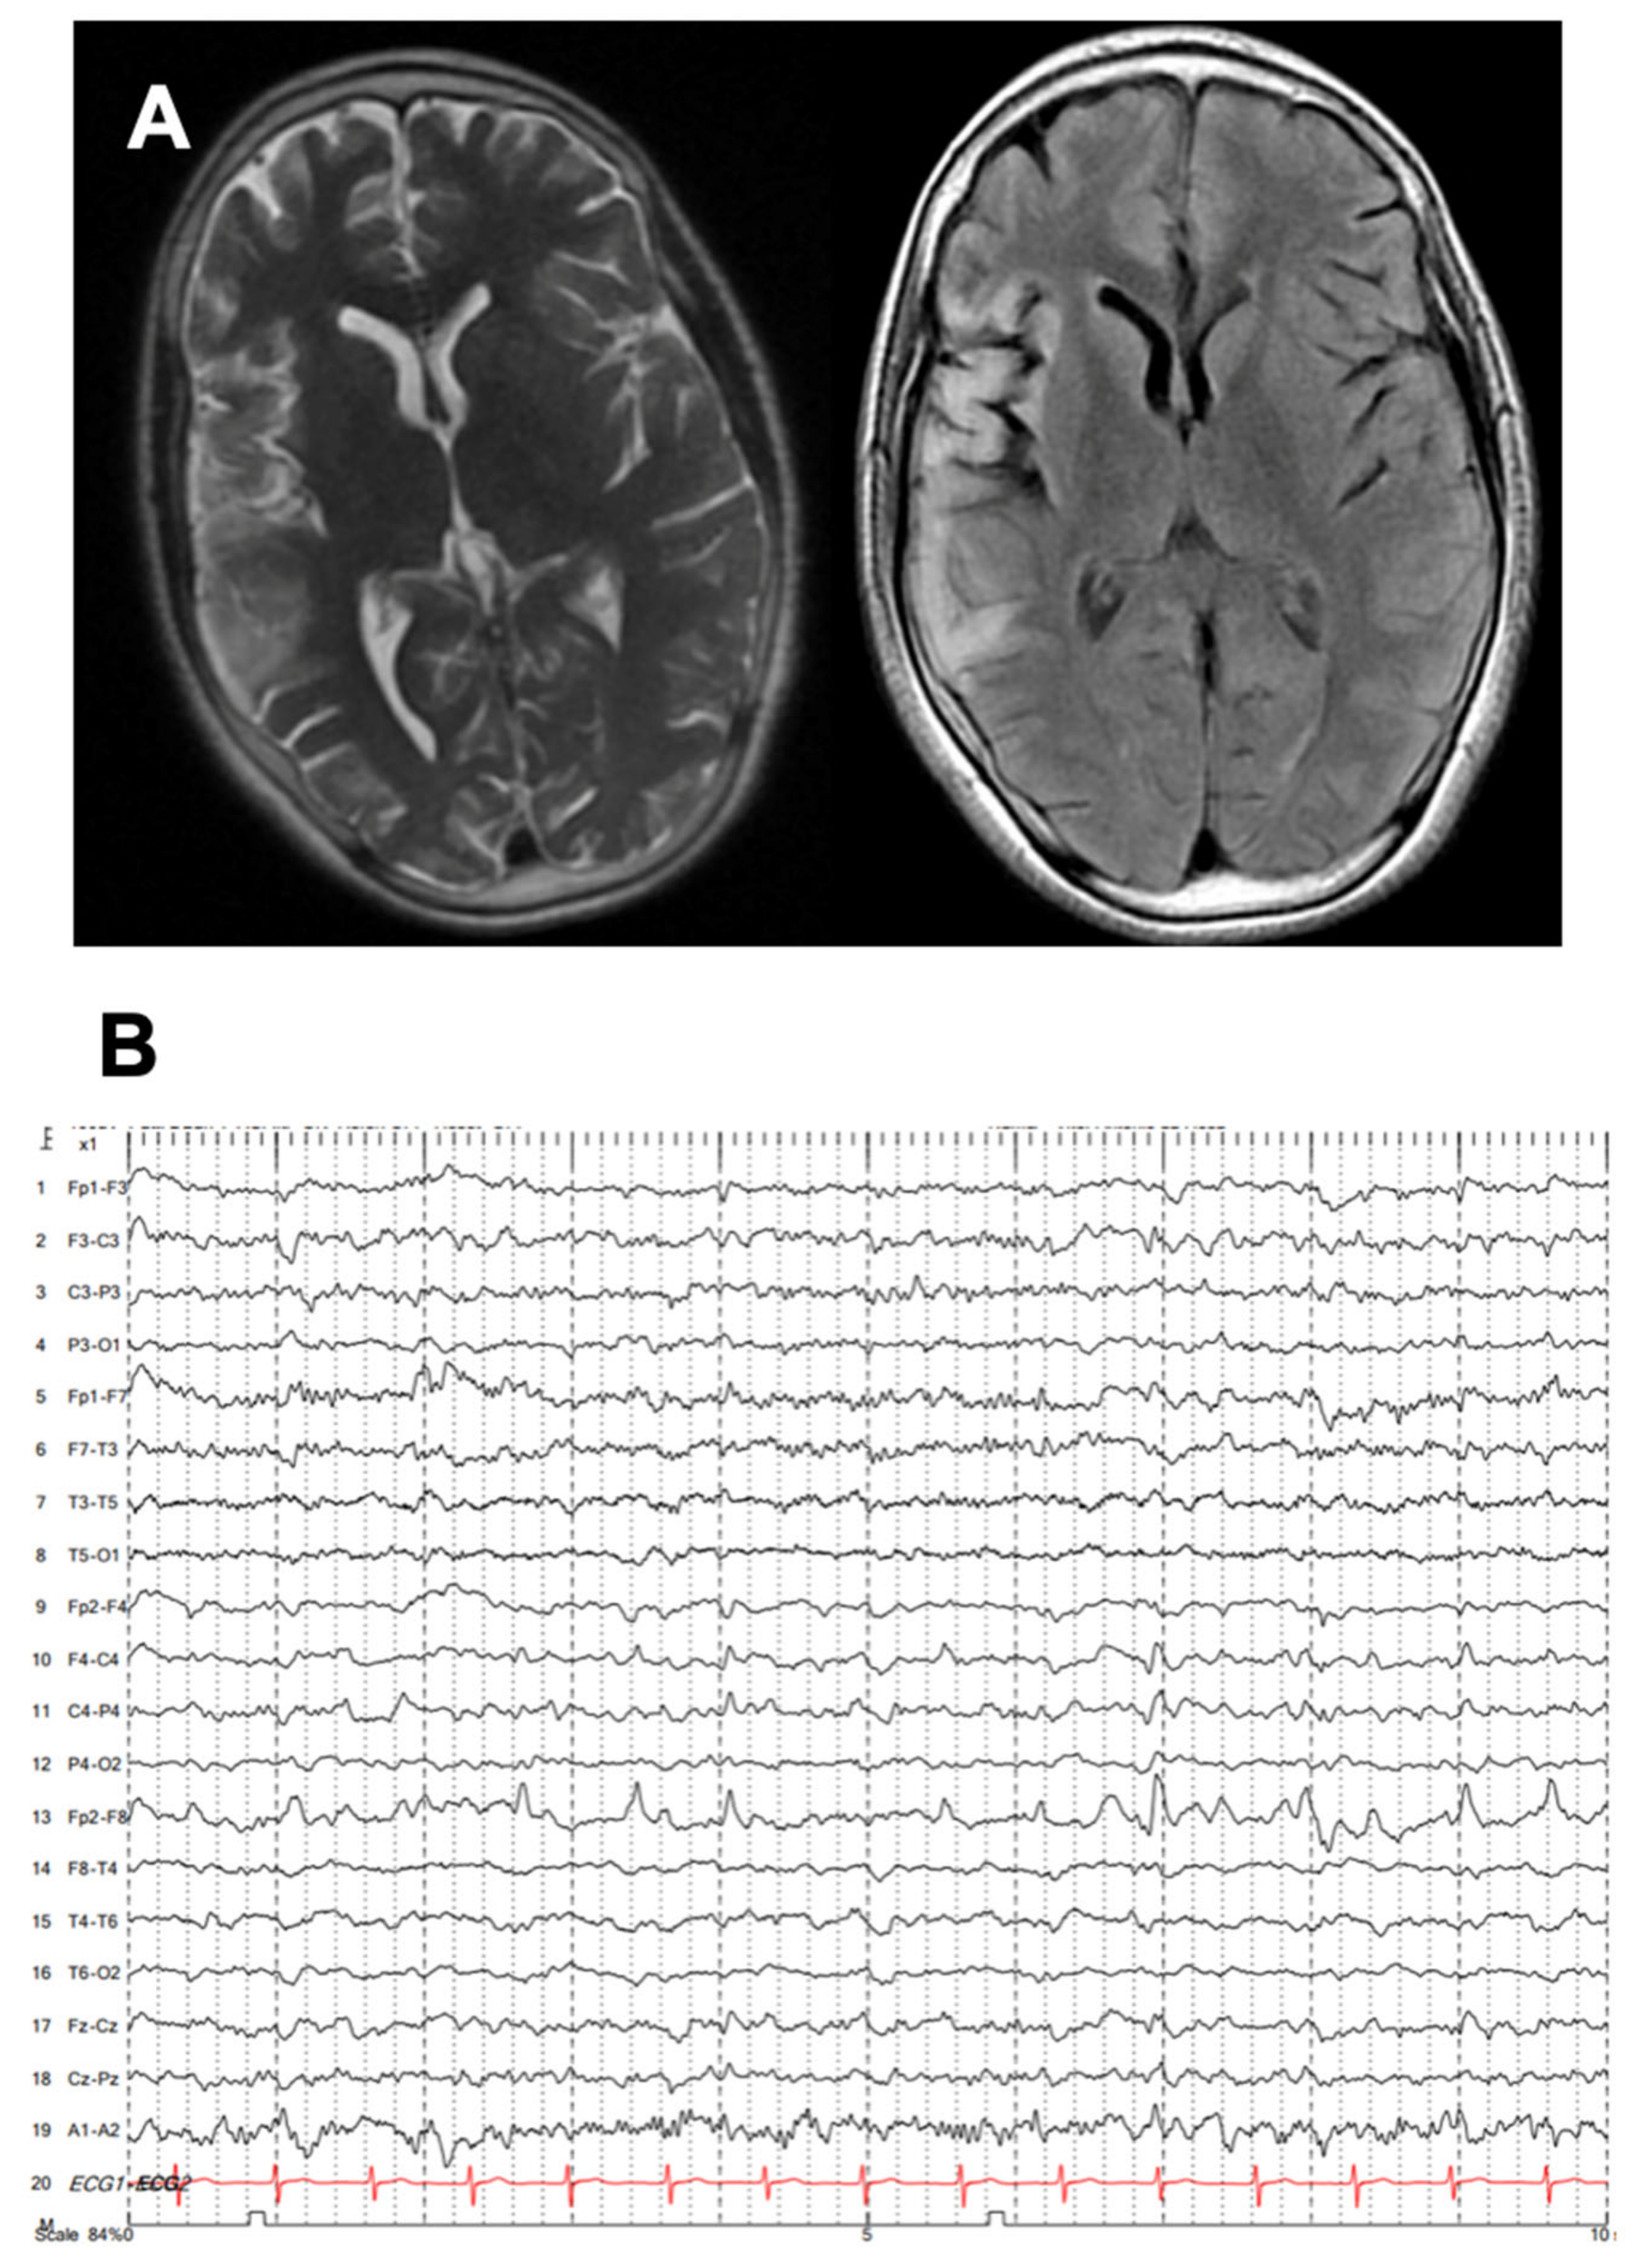

Carbamazepine and lacosamide were added on with no improvement, and he developed progressive weakness in his left arm and leg. There was no family history of epilepsy. He was then referred to our tertiary epilepsy center, at which time neurological examination showed spastic left hemiparesis and moderate to severe dysarthria, with continuous left hemiclonic motor seizures (epilepsia partialis continua [EPC]). By arrival, his MRI showed progressive right hemisphere and caudate atrophy, as well as hyperintensities in the right temporal and frontal lobes, extending throughout the right insula (Figure 1A). EEG also showed progressive slowing in the right hemisphere with periodic sharp waves over the right frontotemporal and parietal regions as well as frequent electrographic seizures (Figure 1B).

Figure 1. MRI and EEG from RE patient. (A) Representative MR images highlighting T2 and T2 FLAIR. Hyperintensity in the right frontotemporal-insular region suggests subacute encephalitis with some degree of cortical atrophy. (B) Representative EEG with continuous rhythmic activity detected in the Fp2-F8 region.